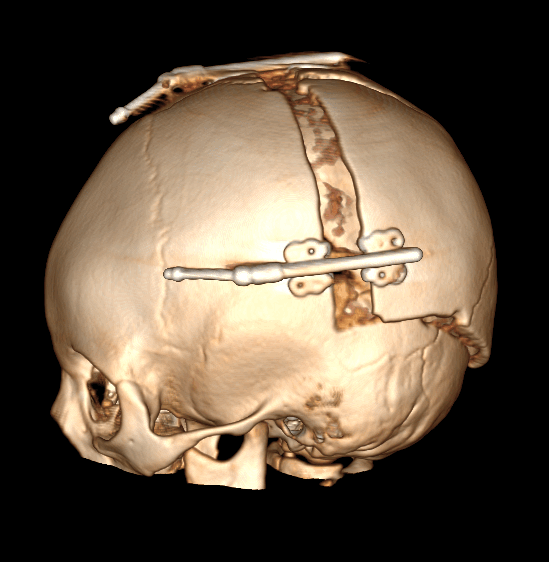

Брахиоцефалия – (от греч. brachy – короткий) возникает в следствии синостозирования коронарных швов с 2-х сторон. Характеризируется укорочением в передне-задних отделах и компенсаторным удлинением вверх в височных костях.

Метод лечения, также является хирургическим. При данной форме краниосиностоза используются дистракторы (выдвижная система), с помощью которых в течение 20-30 дней (ежедневно на 0,1-0,2мм) увеличивается объем черепа. По окончанию срока и удовлетворительному результату, данная система удаляется.

Рис. № 6 Брахиоцефалия

а) - до и после операции

б), в) - СКТ снимки после установки дистракторов.